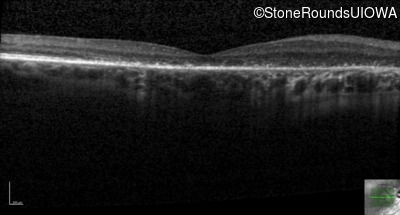

Age at visit: 58 years

OD OS

This 58 year old woman first noticed a gap in the vision of her left eye at age 46.

Age at visit: 58 years (Visit 2)